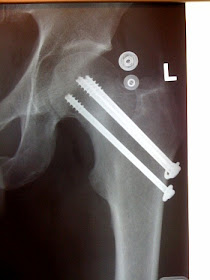

Brian sent me these photos. I have a hard time looking at them, looks very painful. He says:

Guardrail 1. BMC/femur: 0

Healed fasted. Rode Alpe D'Huez 4 months to the day of the accident.